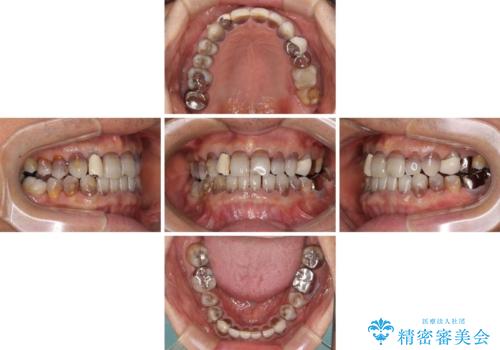

- 前歯のクロスバイトを気にして来院された患者様です。

骨格的に下顎が前方位ではありますが、歯並びが改善されれば正常咬合となることが分かったため、インビザラインを用いて咬み合わせを改善していくこととしました。

インビザラインは四六時中上下のマウスピースを介した咬合状態となるため、治療過程にて奥歯が接触しないという状態が続くことがあります。

奥歯の非接触は機能面において大きな障害であるため、この問題を解決しない限り矯正治療を終えることはできません。

インビザラインでの矯正治療が長期化してしまう要因の1つです。